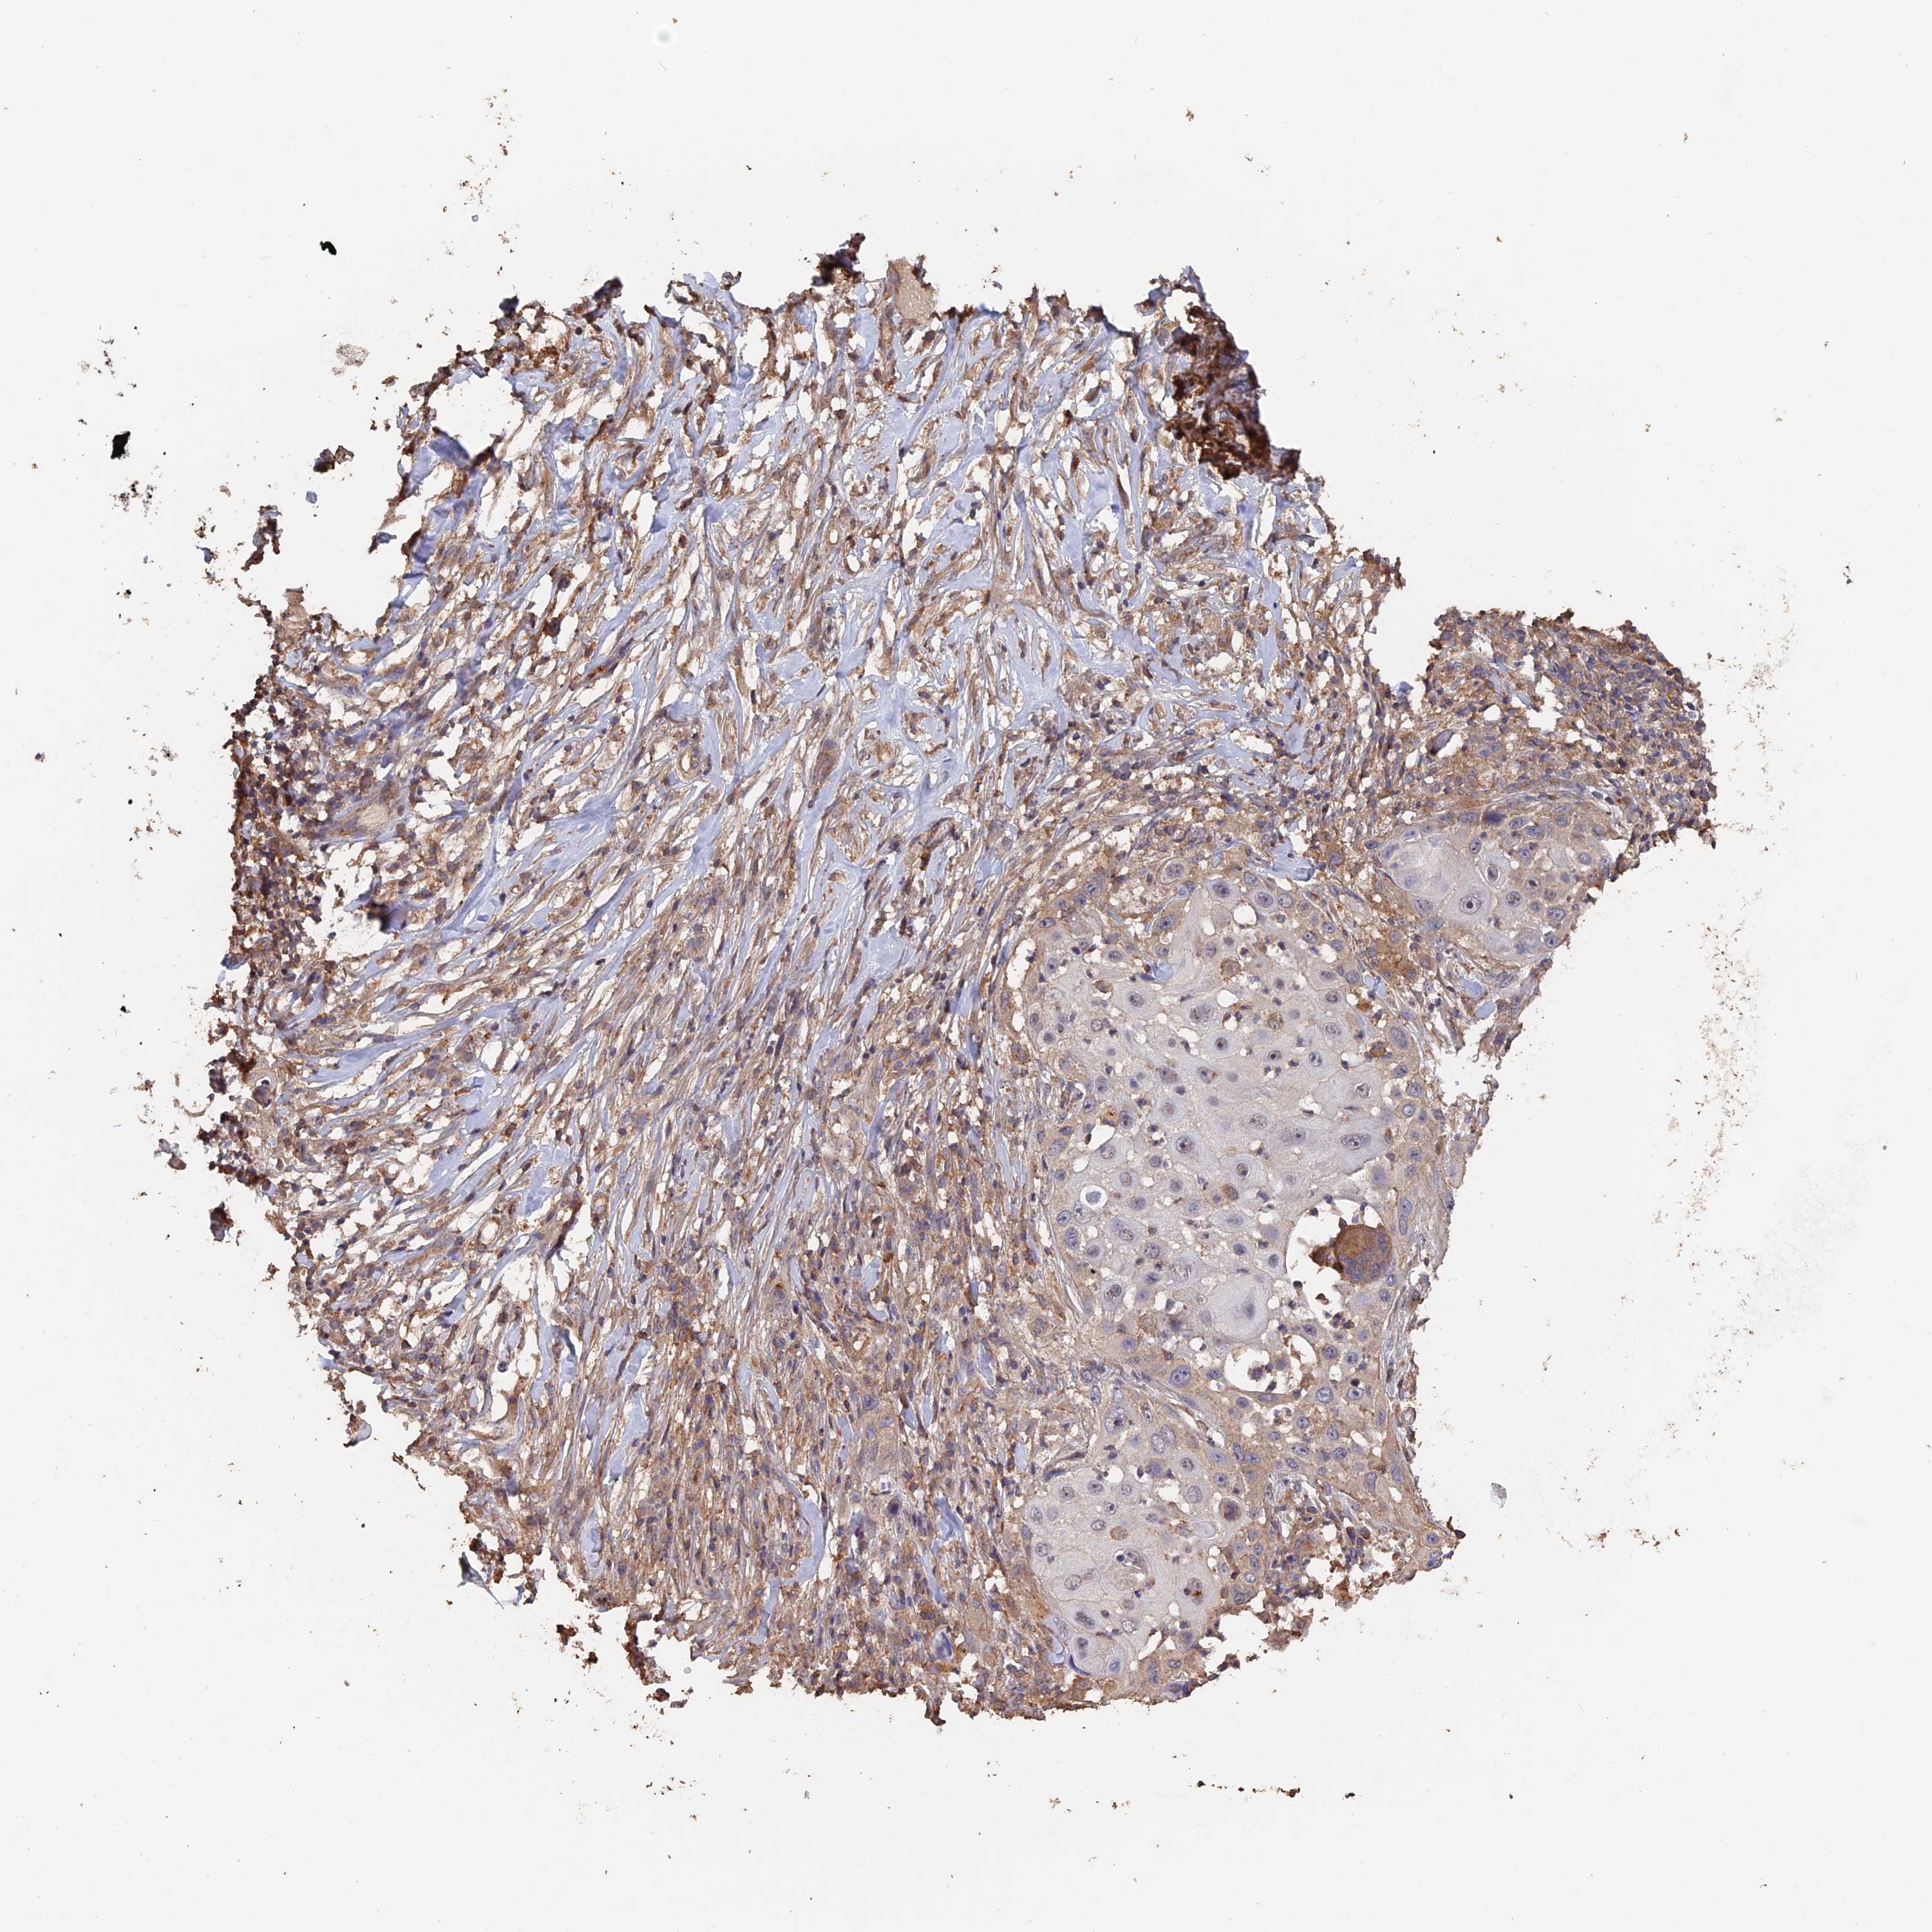

CANCER SKIN CANCER Show tissue menu

Basal cell and squamous cell cancer

SKIN CANCER - Protein expressioni

A mouse-over function shows sample information and annotation data. Click on an image to view it in a full screen mode. Samples can be filtered based on level of antibody staining by selecting one or several of the following categories: high, medium, low and not detected. The assay and annotation is described here.

Each image is clickable and will lead to virtual microscopy that enables deeper exploration of all samples and also displays staining intensity scores, fraction scores and subcellular localization as well as patient and tissue information for each sample.

Antibody HPA039105

Basal cell carcinoma

Squamous cell carcinoma, NOS

Squamous cell carcinoma, metastatic, NOS